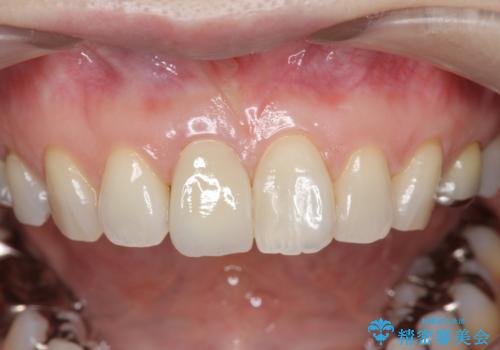

前歯の変色 セラミック審美補綴

以前に神経が死に、根管治療を行った歯の変色が認められたためセラミックによる審美補綴治療を計画します。

- 16万円(仮歯・ファイバーコア・ジルコニアクラウンスペシャル)費用は治療当時の料金となります

神経治療を行い補綴(かぶせもの)治療を行わないと、変色が目立ち審美障害を起こすことがあります。

このような場合、セラミックによる審美改善が治療の一案として提案されます。